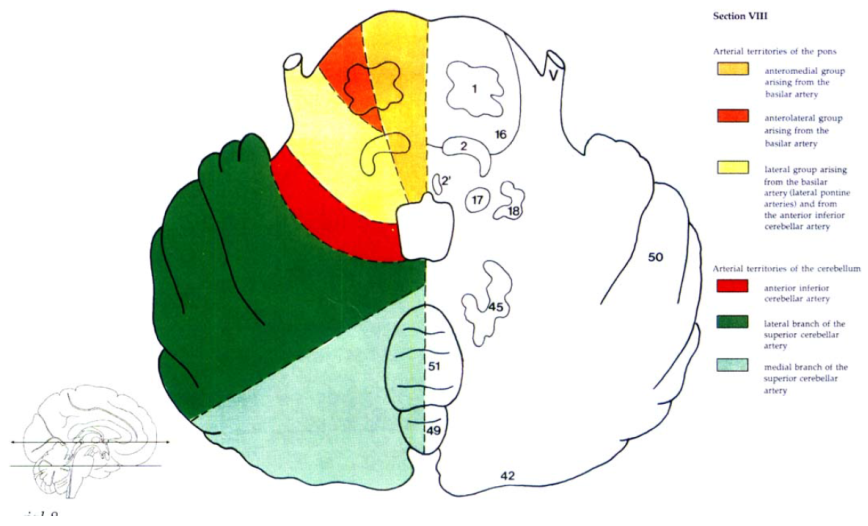

Cerebral vascular territories

Brainstem